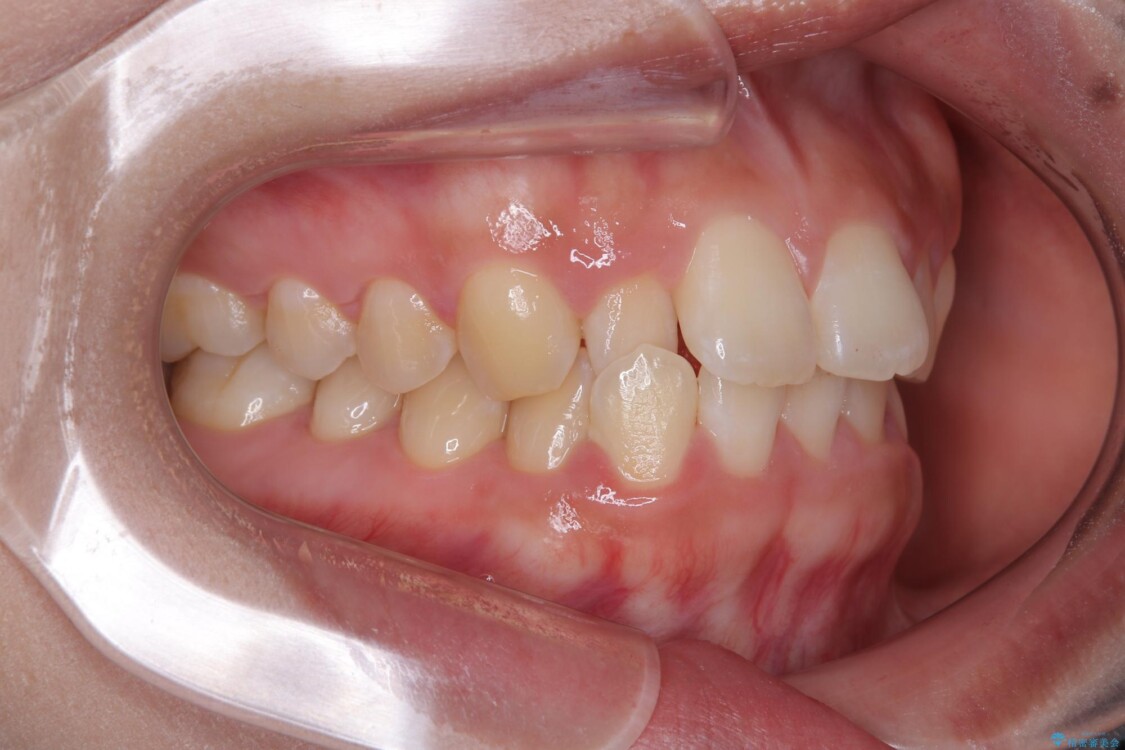

歯列アーチが狭くスペース不足により前歯がデコボコしている状態でした。見た目を改善しつつ、前歯を前方に突出させず、自然な笑顔を目指したいというご希望でした。

・アーチを側方に拡大して歯が並ぶスペースを確保

・抜歯は避け、非抜歯での対応

治療途中

• 目立ちにくい表側装置で1年完了!狭いアーチを側方拡大し前歯のデコボコを整えた症例 治療途中画像